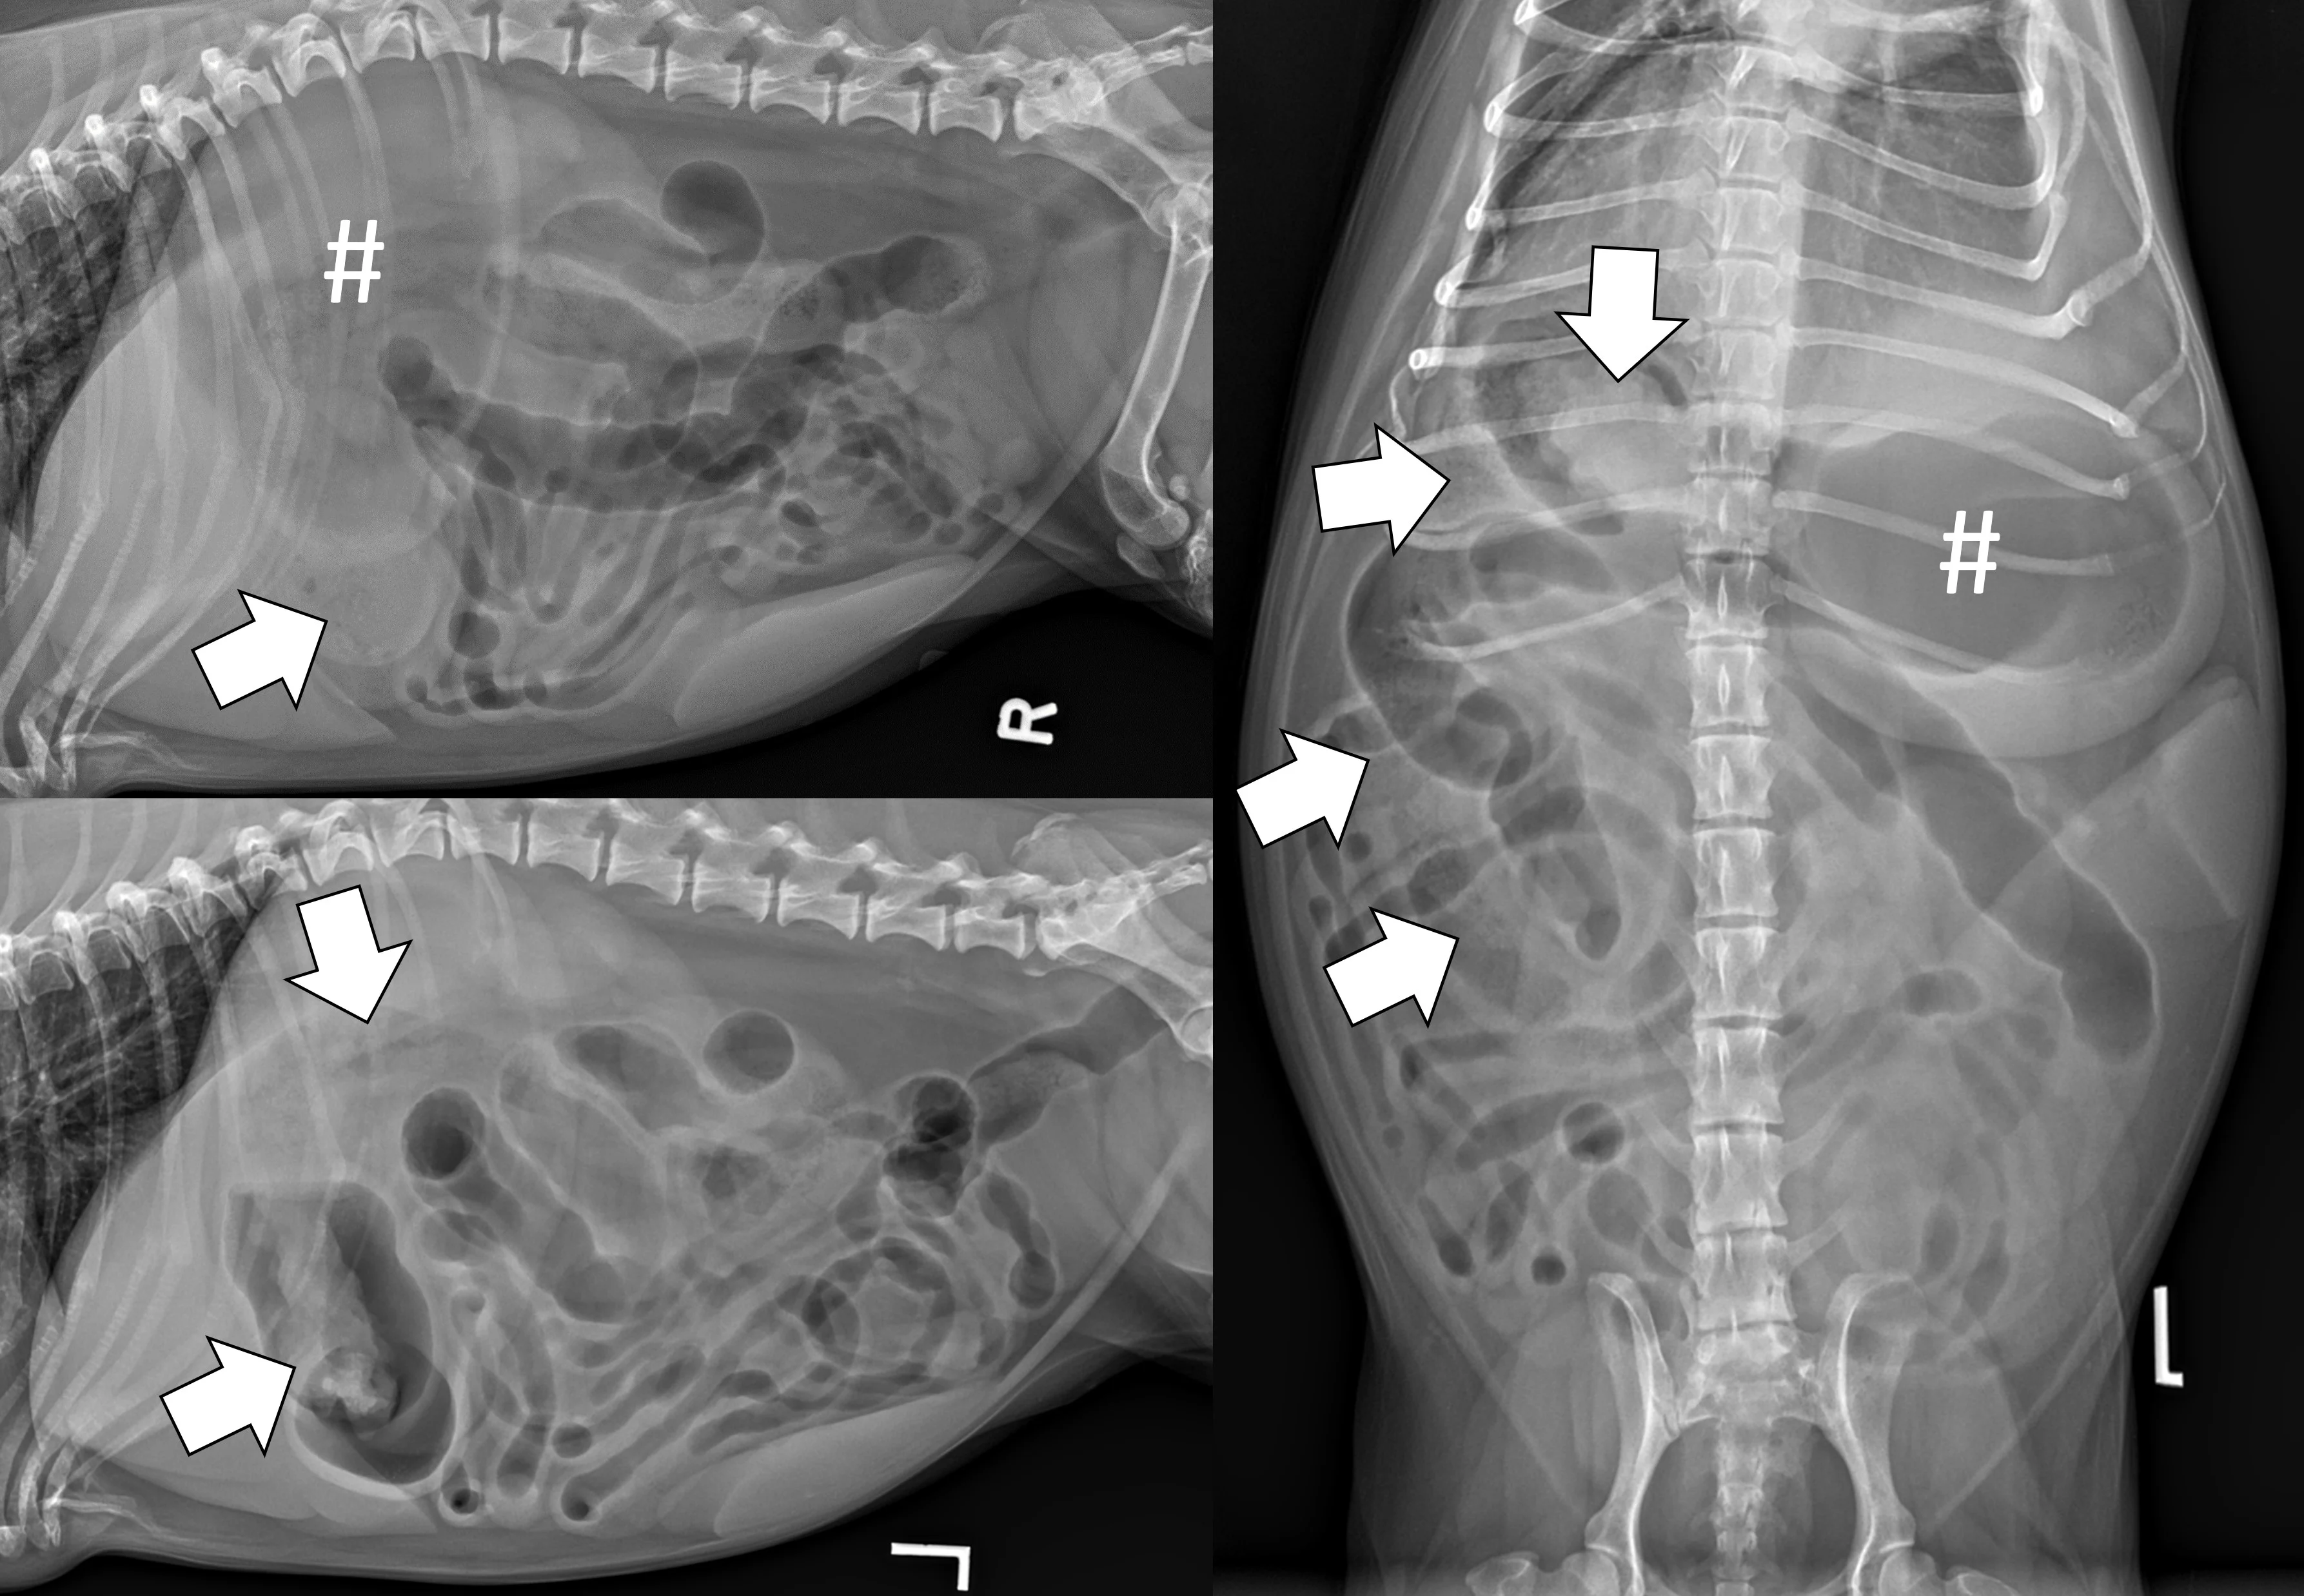

Evaluate the peritoneal space for decreased serosal detail and/or free gas, the combination of which strongly suggests septic peritonitis secondary to GI perforation (Figure 2).

Right lateral and ventrodorsal abdominal radiographs of a 10-month-old neutered male pit bull with a small intestinal mechanical obstruction of undetermined etiology. The stomach is moderately dilated with fluid and gas (pound signs), and there is moderate segmental dilation of the small bowel with stacking and hairpin turns (asterisks). Peritoneal serosal detail is diffusely decreased with a small, tear-drop–shaped intraperitoneal gas bubble between the liver and stomach (arrow) consistent with septic peritonitis secondary to presumed GI perforation.

Small intestinal mechanical obstructions occur when a foreign body blocks the lumen of any segment of the small bowel, causing segmental dilation located orad to the foreign body. As the small bowel increases in size, it becomes crowded in the peritoneal space and begins stacking on itself with sharp, hairpin turns (Figure 4).1 Dilated portions of the small bowel usually contain a mixture of fluid and gas. Occasionally, intraluminal gas may outline part of a foreign body, making the object easier to see. Although the diameter of the small intestine can be objectively measured and compared with the height of the center of the L5 vertebral body,6,7 one study found that using the small intestinal diameter:vertebral body height ratio did not increase the diagnostic accuracy for mechanical obstruction on radiographs regardless of clinician experience.8

Right lateral and ventrodorsal abdominal radiographs of a 1-year-old neutered male domestic shorthair cat with a small intestinal mechanical obstruction from a surgically confirmed earplug lodged in the distal jejunum. The stomach is mildly dilated with fluid and gas (pound signs). Segmental fluid and gas dilation of the small bowel with stacking and hairpin turns can be seen (asterisks). On the ventrodorsal projection, intraluminal gas outlines the margin of the earplug (arrow).